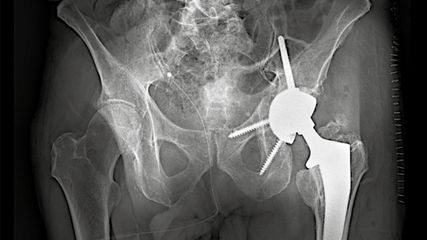

Einzeitiger und mehrzeitiger septischer Endoprothesenwechsel

Die periprothetische Infektion (PPI) stellt eine der gefürchtetsten Komplikationen im Bereich der Orthopädie und Traumatologie dar. Sie ist verbunden mit hohen Morbiditäts- und ...